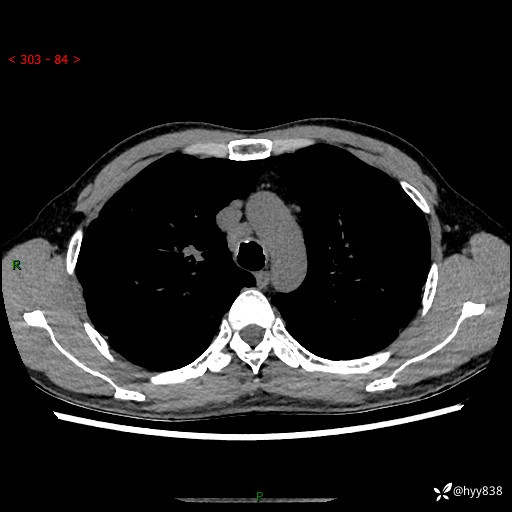

中年男性,咳嗽咳痰1月余。细看:肺、肺门、气管,貌似都有问题---(有结果)

现病史:患者于1个月前受凉后出现间断性咳嗽,伴白色泡沫样痰,无发热寒战、咯血、胸痛胸闷、恶心呕吐、呼吸困难等特殊不适,起初未予特殊处理,后患者就诊当地中医医院,查胸部CT提示支气管炎并双肺感染性病变,经抗感染(哌拉西林舒巴坦),止咳化痰(溴己新、三拗片)等治疗后,患者自诉咳嗽咳痰症状较前缓解,未诉发热等其他特殊不适,近期复查CT提示“肺部感染灶未见消退,双侧肺门增大,双肺散在小结节”,今为求进一步诊治,前来我院就诊,门诊以“肺部感染”收住入院。 患者自起病来精神、食欲、睡眠尚可,大小便正常,体力、体重无明显变化。

胸部CT平扫+增强(两期)